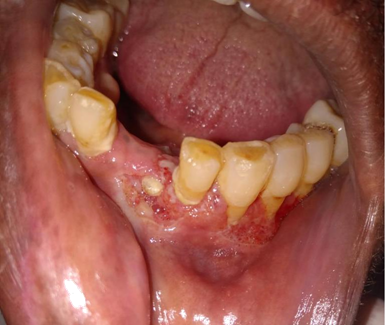

In the course of medical care, the patient also complained of pain in teeth and was referred to the dentistry service. Upon dental examination, it was possible to notice a moriform aspect lesion in the gingiva and alveolar ridge of the mandible (region corresponding to teeth 33 to 36) with diagnostic hypotheses of paracoccidioidomycosis, histoplasmosis and oral squamous cell carcinoma and an incisional biopsy of the lesion was performed (Figure 1).

Figure 1 Clinical aspect of the oral lesion.